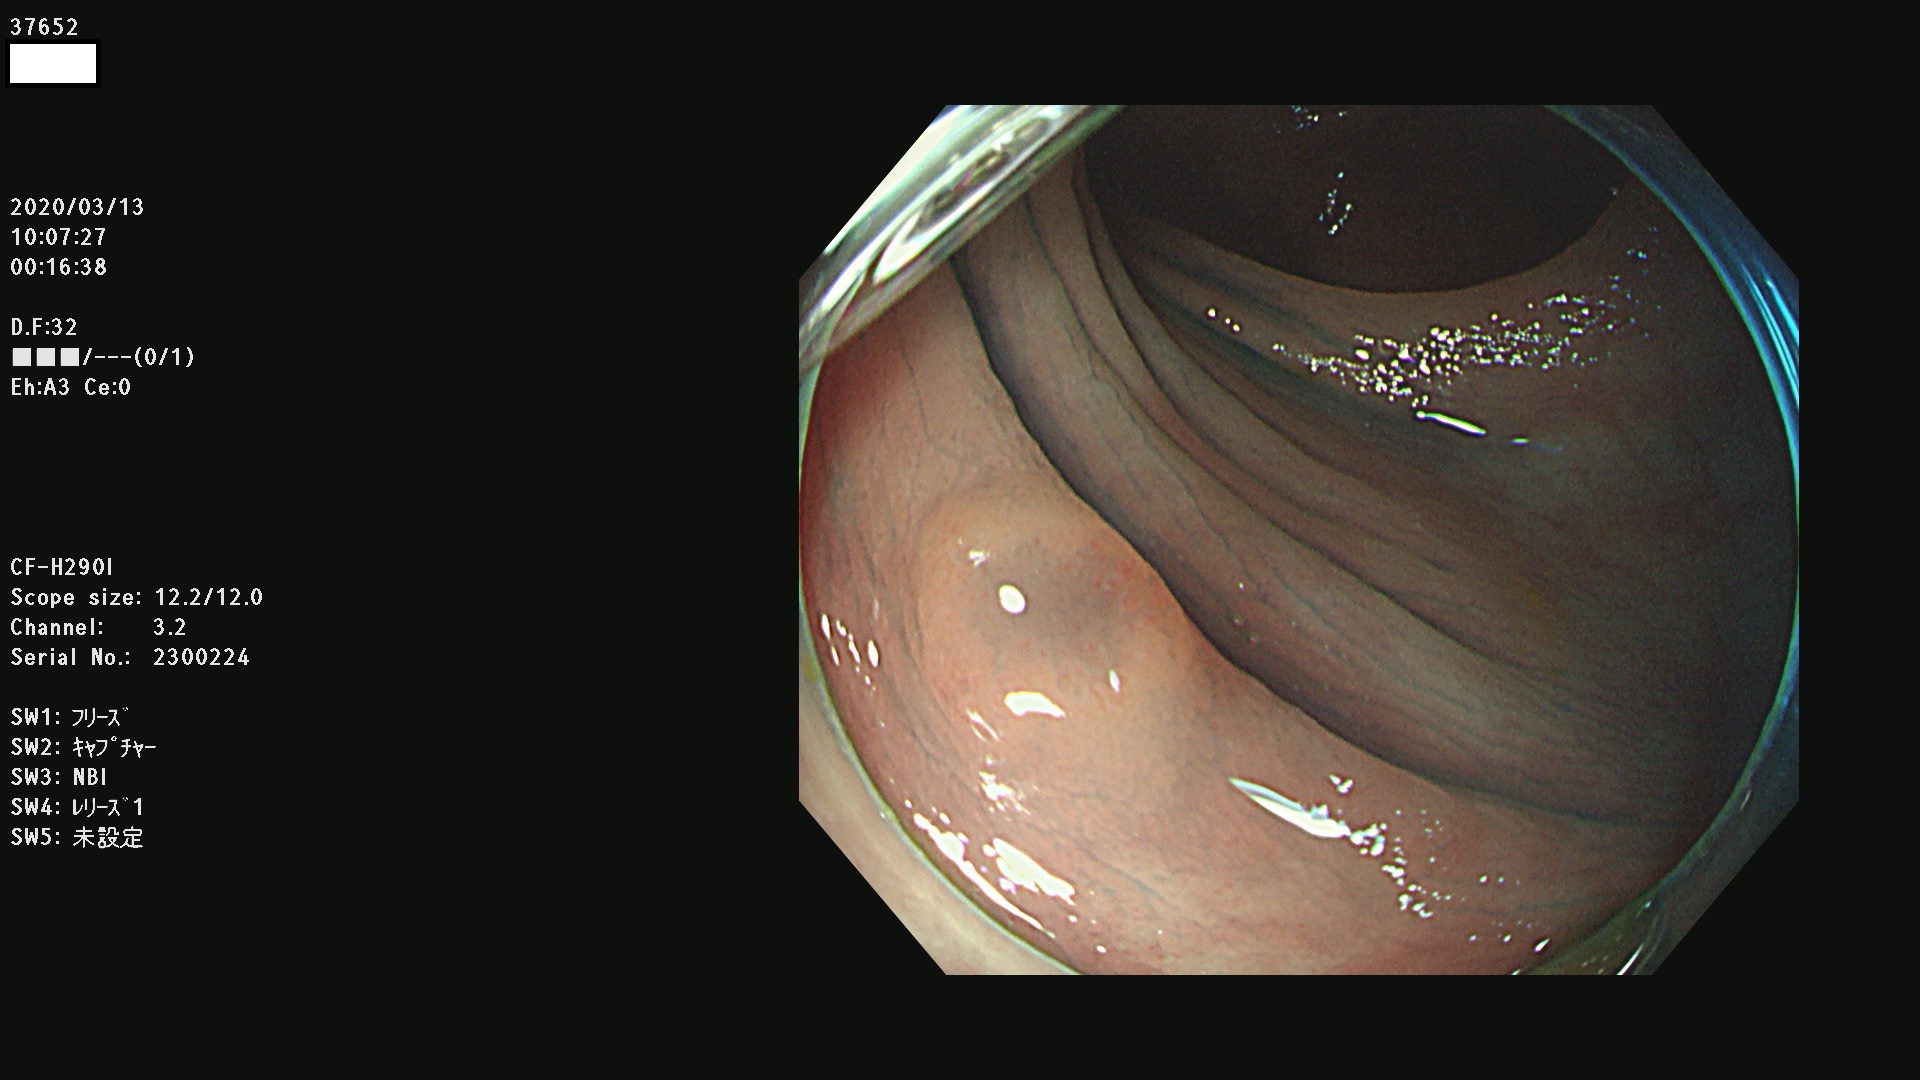

37600 37601 37602 37603 37604 37605 37606 37607 37608 37612 37614 37616 37618 37619 37620 37621 37622(SSAPのみ) 37623(SSAPのみ) 37624 37626 37627 37628 37629 37632 37633 37635 37636(SSAPのみ) 37639 37640 37641 37642 37643 37644 37647(SSAPのみ) 37648 37649 37650 37652 37653 37655 37657 37659 37660 37662 37664 37666 37668(SSAPのみ) 37670 37671 37672 37676 37677 37678 37679 37680 37682 37684 37685(SSAPのみ) 37686 37687 37688 37689 37690 37691 37692(SSAPのみ) 37693 37694 37695 37696 37697 37699

発見困難で危険性の高い平坦型病変(上記100名より抽出)